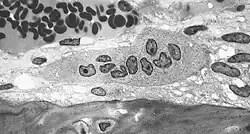

Osteoklasty są wielkości ok. 100 μm, mają zwykle kształt owalny. Są polikariocytami, mają 5-10 jąder komórkowych. Ich cytoplazma jest kwasochłonna i bogata w lizosomy, mitochondria i polirybosomy. Na powierzchni komórek znajduje się wiele wypustek cytoplazmatycznych, zwiększających powierzchnię ich styku z macierzą międzykomórkową kości.